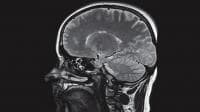

3D Ultrasonic Neuronavigation System for Image-Guided Brain Surgery

This GPS-like system could help surgeons navigate through the brain to find and remove everything from tumors to bullet fragments easily, cheaply, and with hardly any cutting. The ultrasonic-based locational system was designed with neurosurgeon Sumeer Lal.

The neuronavigation system, adapted from one developed some years ago to track robots, eliminates cameras and replaces them with a head restraint from which ultrasonic sensors branch off like tree limbs. It also adds sensors to the surgeon’s probe. The two sensors on the probe act as transmitters while those on the head restraint serve as receivers, allowing the equipment to map the probe’s movement through the brain in three dimensions.

Because the receivers that replace the cameras take up much less space, sightline problems don’t occur. And because they remain in place — not on the patient’s head, but close by — recalibration in a sterile environment is easier. The new system has sub-millimeter accuracy, which should make the system more attractive to neurosurgeons. Hospitals can pay as much as $500,000 to $750,000 for standard image-guided neurosurgery equipment. The cost of the new system would be significantly less — perhaps $50,000 to $75,000.